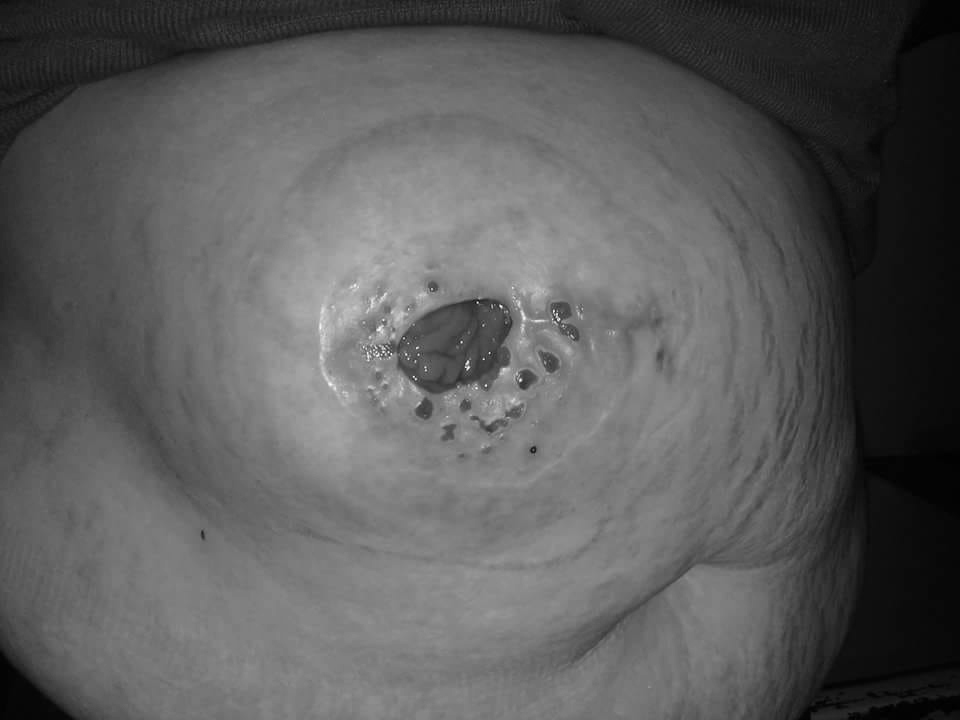

Este fue el caso de Yasna Cortés Cáceres (31), quien decidió operarse las trompas de Falopio en el Hospital de Quilpué. Quería ligárselas para no tener más hijos aparte de los cuatro que ya tiene -esto al menos por un tiempo-. Sin embargo, jamás imaginó que la intervención saldría mal y quedaría con un grave e incómodo problema: hoy en día defeca por la vagina.

A causa de esto, arrastra una bolsa médica que le permite realizar sus necesidades por la boca del estómago y evitar el tránsito hacia su zona vaginal. Estas bolsas tienen un valor elevado: cada una cuesta $4 mil y debe utilizar tres o cuatro al día. Es decir, gasta alrededor de $400 mil mensuales solo en este utensilio médico.

En conversación con CHVNoticias.cl, Cortés Cáceres contó detalles de la intervención en la que le extirparon las trompas de Falopio sin su autorización. A esto, se agregó una fístula que quedó tras un corte que sufrió en plena cirugía.

Con temor, Yasna confiesa que la complicación más grave, además de la incertidumbre de si podrá tener hijos nuevamente, es lo que sucede en su intestino grueso, ya que, de alguna manera, el corte y la misma operación le provocaron una inusual anomalía en su cuerpo que la obliga a expeler materias fecales por su vagina.